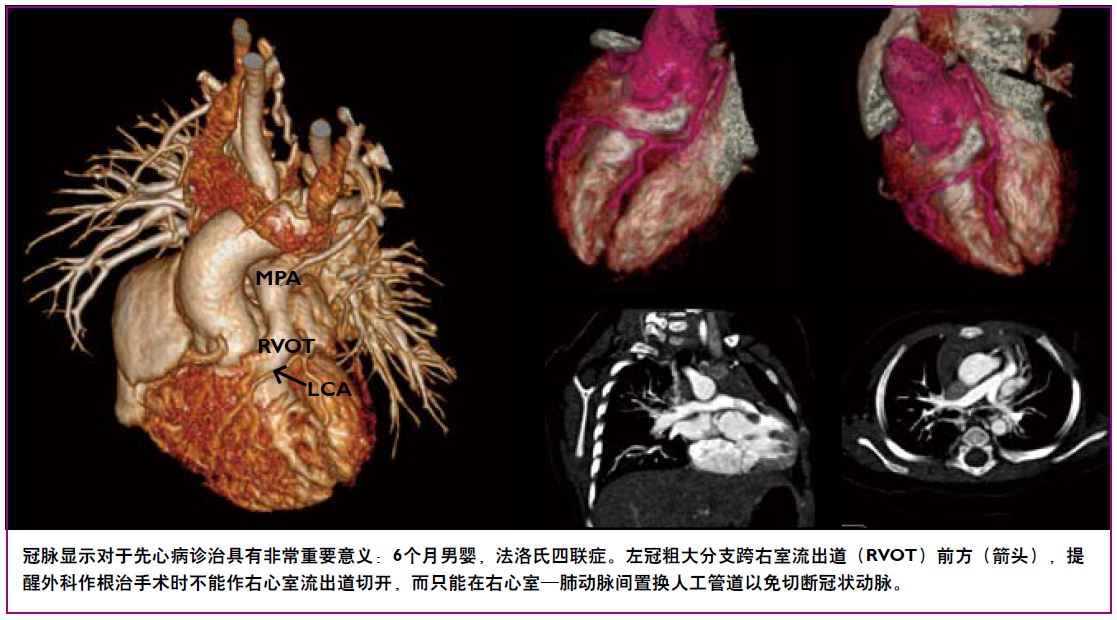

凭借0.27秒/圈极速旋转,8厘米宽体覆盖以及完善的解决方案,极速CT令心脏检查驾轻就熟。